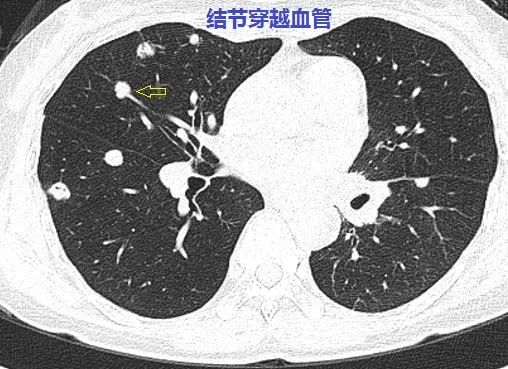

这个与血管相连的双肺多发小结节是怎样的神奇疾病